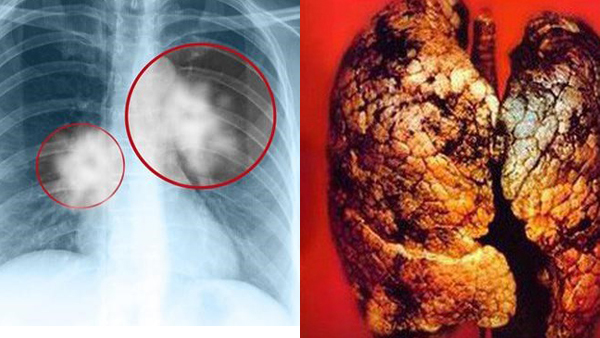

Những triệu chứng và phòng ngừa ung thư phổi

Ung thư phổi rất khó phát hiện ở giai đoạn đầu, mà thường phát hiện ở giai đoạn muộn khi đã hoành tráng rất nặng. Tuy nhiên, việc kiểm tra sức khỏe và xác định nguy cơ mắc bệnh thường xuyên sẽ giúp giảm thiểu nguy cơ bị ung thư phổi.

Nếu bạn gặp bất kỳ triệu chứng nào đáng ngờ về ung thư phổi, hãy đến bệnh viện để được khám và chẩn đoán kịp thời. Điều này rất quan trọng để tránh bệnh trở nên nguy hiểm và tiềm ẩn nguy cơ tử vong. Chính vì vậy, việc phát hiện sớm và chẩn đoán đúng bệnh là cách tốt nhất để đảm bảo sức khỏe và giữ gìn cuộc sống của mình.